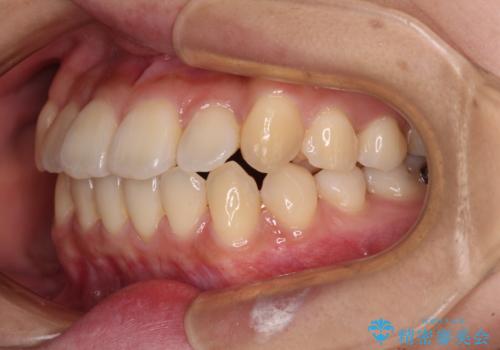

- 八重歯や前歯の捻転とクロスバイトが気になり、インビザラインによる矯正治療を希望して来院された患者様です。

上顎側切歯(上の真ん中から2番目の歯)が舌側転位している場合、無理して動かそうとすると歯髄壊死を起こすリスクが高い印象があります。

インビザライン単体でも治療は可能ですが、安全策としてインビザラインで歯列を移動する前に上顎前歯をワイヤー矯正で整え、その後上下歯列をインビザラインにて矯正治療を行うこととしました。

舌側転位している側切歯特有の、切縁の位置が不揃いであったり、根元が内側に引っ込んだ状態であったりという、インビザライン独特の仕上がりになることなく、きれいに整った歯列とすることができました。